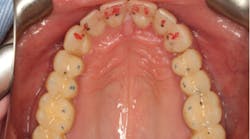

After assessing the results from the complete exam, we obtained complete records, including facebow-mounted models and a complete photo series. We started developing a treatment plan with Darren’s time and financial constraints in mind. This began with a two-dimensional workup to evaluate Darren’s occlusal stability, global esthetics, and macro esthetics.

From the two-dimensional evaluation, the signs of occlusal instability were clear. Darren had very thin, chipping incisal edges, to the point where they were becoming transparent. The patient had almost worn shelves into the lingual of the maxillary anteriors, suggesting a restricted envelope of function. He also had wear into dentin in the anterior teeth as well as posterior teeth, and his anterior teeth had Class 1 mobility.

Our two-dimensional evaluation allowed us to create our three-dimensional treatment plan with a diagnostic wax-up on mounted models. After reviewing all findings, Darren was brought in for a treatment planning consultation.